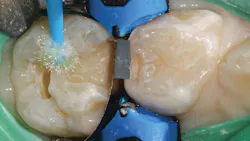

A selective-etch technique with 35% phosphoric acid is used to achieve the highest possible bond strengths.6,7 The etchant is washed and the tooth is dried without desiccating it. A universal bonding agent (Futurabond U, Voco) is rubbed onto the tooth surface for 20 seconds (figure 3), and thenThis is a modified snowplow technique, in which the flowable base layer is light cured in combination with placement of 4 mm of the restorative material.8,9 This allows the flowable to extrude up to the occlusal surface and down to the gingival margins, filling any voids.